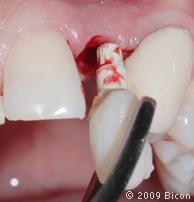

26. Для раскрытия верхнего бокового правого резца сделан надрез.

27. Извлечение заглушки с помощью специального инструмента.

28. Извлечение заглушки с помощью специального инструмента.

29. Удаление излишков мягких тканей, которые могут препятствовать правильной установке трансфера, производится посредством слепочного римера размером 3 мм, вращаемого вокруг направляющего штифта.